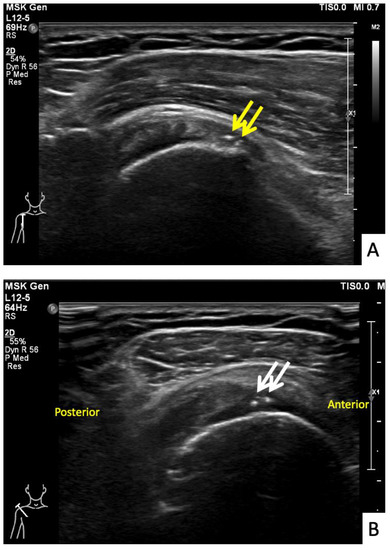

The sixth case was a 64-year-old Thai male who had received his first dose of AstraZeneca vaccine. The vaccination landmark was 3 fingerbreadths below the acromial process with a needle direction of 30 degrees cephalad to the skin. He had developed right shoulder pain with limited range of motion in all directions within 48 h of receiving the vaccine. He did not take any medications, and when the symptoms had not improved in a month he decided to see an orthopedist. A physical examination showed tenderness at the deltoid muscle with limited range of motion in all directions. An ultrasonography showed tenosynovitis at the long head of the biceps and a low-grade partial tear of the subscapularis tendon (Figure 7A,B). He was treated with oral prednisolone (30 mg/day) for 5 days and an intraarticular steroid injection (triamcinolone acetate (TA) 40 mg/mL). His shoulder pain gradually improved, and he could return to normal activities within 7 days after treatment.

Figure 7.

Ultrasonographic images of the right shoulder of Patient 6. (A) A transverse ultrasonographic image over the lesser tuberosity of the right shoulder with the patient in the external rotation position showing a small, partial thickness, intrasubstance tear (yellow arrow) at the footprint of the subscapularis tendon. (B) A transverse ultrasonographic image over the bicipital groove with the patient placing his hand palm up in supination on his leg showing surrounding fluid (white arrow) within the long head biceps tendon sheath, indicating tenosynovitis.